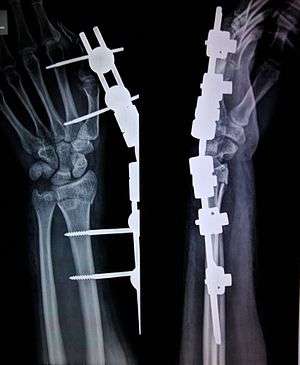

an X-ray image of an external fixator being used for reduction of a broken bone, in this case, a Colles' fracture which involves a fractured radius bone.